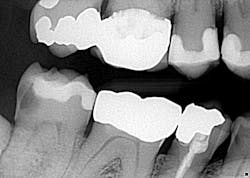

His situation was more involved than anticipated (figures 1–3), which, to address properly, would more or less require a full mouth of crowns, scaling and root planing, and a 360-degree turnaround of his oral health home-care management.

2. The patient has HUGE apple core cavities, large existing fillings with caries, and they all need crowns to restore. I’m more or less at a point in my career when I just don’t do BAFs (big-ass fillings) anymore, and if I do, it’s on a very rare occasion. Why? Because there are limitations to our restorative materials (and my patience!), and if I’m spending 30 minutes trying to get a seal on a resin that wraps around a tooth in 10 different directions, it’s not worth my time and headache. I don’t like putting myself or my patients in a situation where they have to come back again and again for the same thing. They are spending their money two to three times over for restorative work, even if it’s for something to “get them by.” Tough love? Perhaps, but I’m calling the shots here, not the patient.